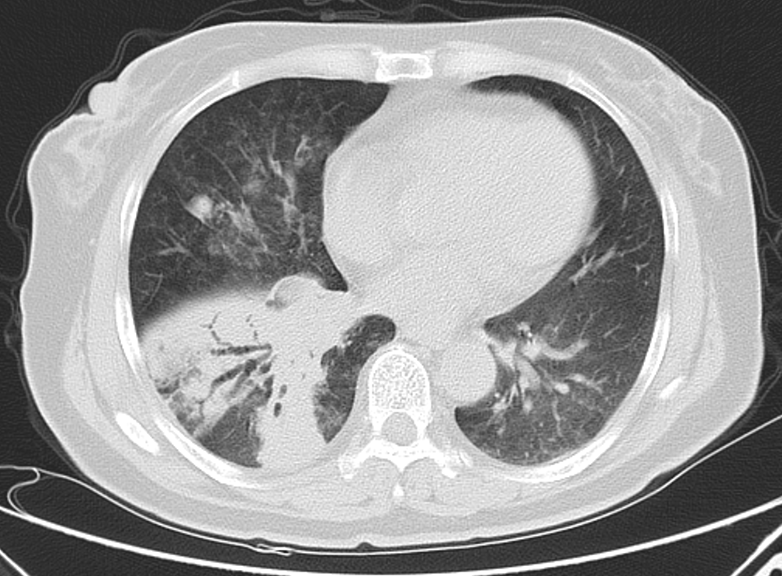

经检查,胸部CT结果显示,卢女士双肺存在多处病变,右中下肺支气管局部已经闭塞;气管镜检查看到,她右下肺的呼吸通道变得狭窄,里面的黏膜又厚又糙,还很红,能看到一些出血点。这种情况下,传统的活检风险较高,可能引发更大出血。

CT检查